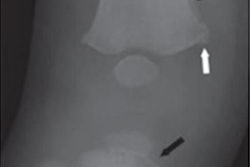

No single injury defines abusive head trauma, so physicians frequently must make a diagnosis based on information collected through clinical histories, physical exams, and laboratory and imaging data. At the same time, medical testimony in legal cases of child abuse can often be contradictory, and the denial of abuse has become a significant medical, legal, and public health problem.

- Relatively few infants with abusive head trauma have isolated intracranial injury without retinal hemorrhages, fractures, or other manifestations of child abuse.

- Infants suspected of having abusive head trauma should be evaluated for other diseases that could present with similar findings.